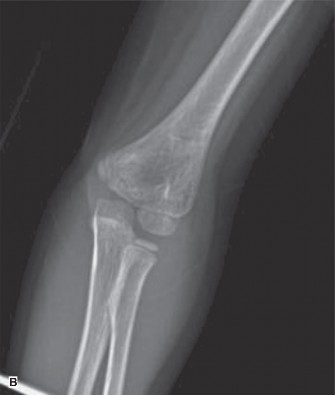

Displaced Supracondylar Humerus Fracture

- Radiographic Findings: AP and lateral radiographs of the left elbow revealed a significantly displaced supracondylar humerus fracture. On the lateral view, the anterior humeral line passed anterior to the capitellum, and Baumann's angle was significantly decreased (less than 45 degrees), indicating severe extension-type displacement with posterior and medial angulation of the distal fragment relative to the proximal shaft. The fracture line was oblique, originating from the olecranon fossa posteriorly and extending anteriorly through the coronoid fossa.

- Classification: Gartland Type III supracondylar humerus fracture (completely displaced). Given the neurovascular compromise (absent radial pulse), this also qualifies as a pulseless supracondylar fracture.

- Decision: Urgent closed reduction and percutaneous pinning (CRPP) followed by a long arm cast.

- Classification: Gartland Type III (completely displaced) with neurovascular compromise (absent radial pulse).

- Rationale: Gartland Type III supracondylar fractures are unstable and carry a high risk of neurovascular injury and compartment syndrome. The presence of a pulseless limb, even if initially warm and well-perfused (pink pulseless hand), mandates immediate reduction to restore perfusion. If pulse does not return after closed reduction, further intervention such as open reduction and exploration of the brachial artery may be necessary. Definitive surgical fixation with K-wires provides stable immobilization, allowing for early pain control and preventing further displacement or complications.